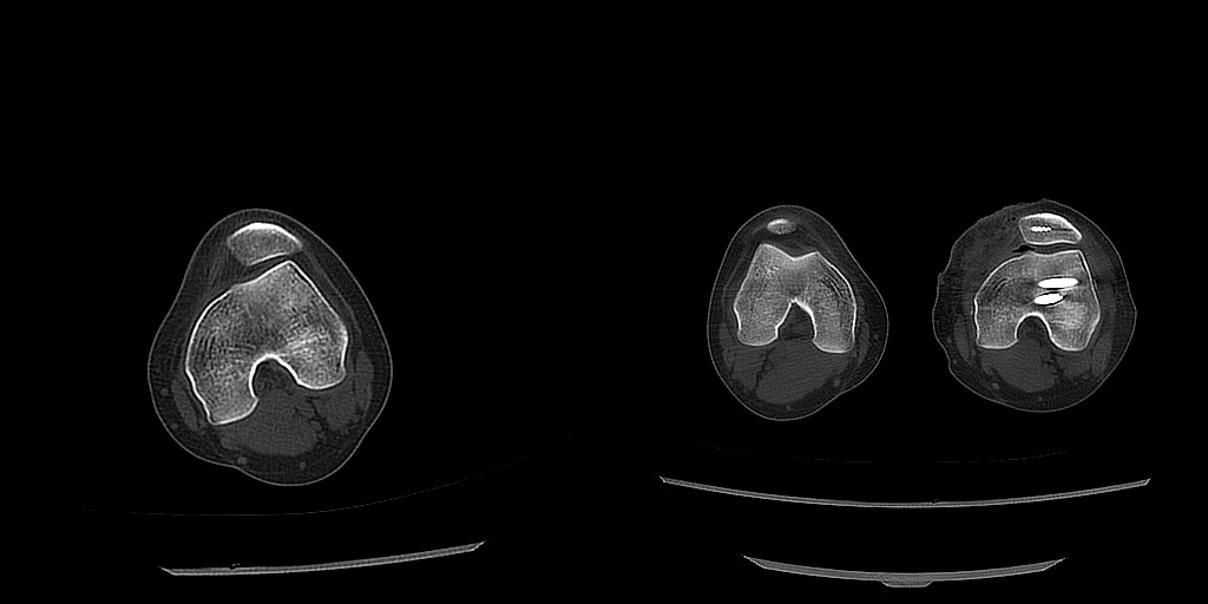

复发性髌骨脱位合并D型滑车发育不良患者因外院初次手术失败行滑车成形+MPFL重建翻修术后

股骨前倾角35°的患者去旋转截骨+MPFL重建术后髌骨回到正轨,关节对位明显改善